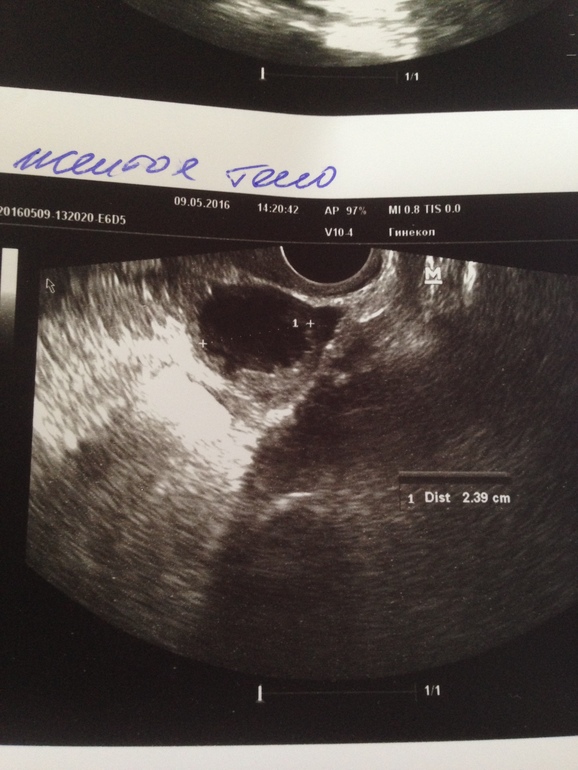

Так вот сегодня на узи врач не увидела жт, эндометрий 1,07 см, зато увидела в правом яичнике анэхогенное включение 2.63 на 1.94 см. Говорит,на жт по размерам не похоже,и написала "Киста правого яичника (фолликулярная)" под вопросом. Назначила прийти после месячных до 7 дц,чтобы посмотреть ушла ли эта киста и если нет, говорит, надо попить цикл-2 противозачаточные,чтобы яичники "отдохнули". Так же по старым узи заметила,что дф у меня зачастую зреет именно в правом яичнике. С чем это может быть связано? Пить ок я вообще не хочу: во-первых,я их никогда не пила и боюсь сбоев (до первой беременности были проблемы с гормонами,сейчас только с ттг), во-вторых,не хочу пропускать циклы планирования, итак уже 9 месяцев не получается.

так вот вопрос вот в чем: может ли это включение все-таки быть желтым телом или все-таки киста? Врач-специалист опытный, раз не сказала,что ЖТ,значит и не жт? вообще я предложила своей гине,что если в след.цикле эта киста уйдет и мы снова увидим хороший дф,нельзя ли сделать укол хгч,чтобы фолик 100% лопнул и случилась овуляция,на что она мне ответила,что я начиталась фигни и что я еще молодая и никакие уколы не нужны. А тем временем часики тикают.....

Жёлтое тело имеет не ровные края и там кровоток смотрят, если есть значит ЖТ, а нет скорее киста. И кисты вроде круглые. А фото вам не дали?